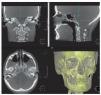

Reconstrucción secundariaEn un segundo proceso de cálculo se pueden obtener más planos de corte a partir de las tomografías axiales obtenidas en la reconstrucción primaria. Entre los métodos principales de reconstrucción secundaria cabe mencionar en primer lugar la reconstrucción multiplanar, que en general debería ser capaz de generar y representar automáticamente cualquiera de los sistemas de software modernos utilizados para el procesamiento de los datos. Normalmente se representan los planos sagital y coronal, que son perpendiculares al corte axial (fig. 11). No obstante, también se pueden obtener reconstrucciones mucho más complejas a partir de una ruta creada de forma manual en el conjunto de datos, por ejemplo7. De este modo, el médico tiene la posibilidad de generar, a partir de un conjunto de datos volumétricos y en muy poco tiempo, una reconstrucción panorámica específica del paciente de estudio o tal vez secciones transversales de la ATM en un plano generado de forma individualizada (fig. 12). En determinados casos esto puede proporcionar mucha más información al médico que la radiografía convencional de la ATM y facilitar de ese modo el diagnóstico y el plan de tratamiento.

Figura 11. Reconstrucciones multiplanares simples. Arriba izquierda: coronal, arriba derecha: sagital.

Figura 12. Cortes de la ATM del paciente creados manualmente.

Existe una variante especial de reconstrucción secundaria que se utiliza más para demostración que con fines de diagnóstico. Se trata de la reconstrucción de sombreado de superficie o SSD (Surface Shaded Display), en la que se interpretan sólo aquellos valores de vóxel que le son más cercanos al observador. De ese modo se genera la impresión de un modelo plástico tridimensional. Dicho efecto se puede intensificar coloreando los distintos tejidos que se pueden diferenciar o configurando una representación transparente de determinadas capas (fig. 13).

Figura 13. SSD (Surface Shaded Display).